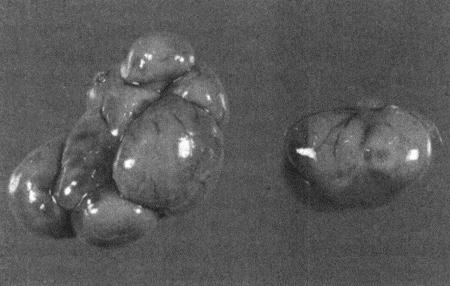

Фиг. 4.15.

Яичники суки при пиометре (около 6 недель после течки). Характерно отсутствие желтых тел (см. Приложение)